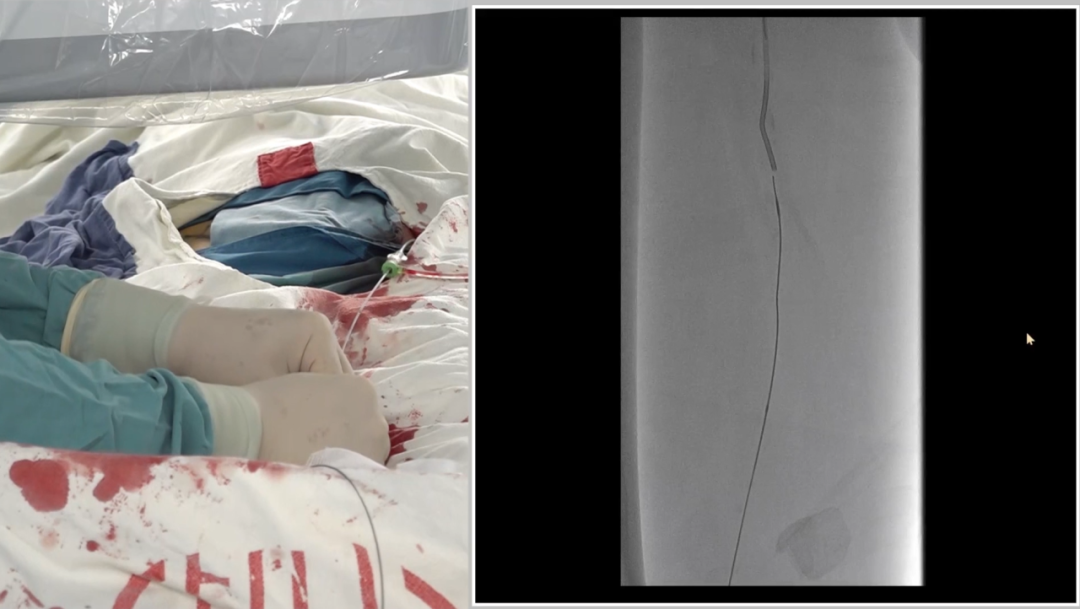

入路选择:左侧股动脉翻山入路

采用常规左侧股动脉穿刺,通过"翻山"技术到达右侧病变区域,为后续操作建立通路。